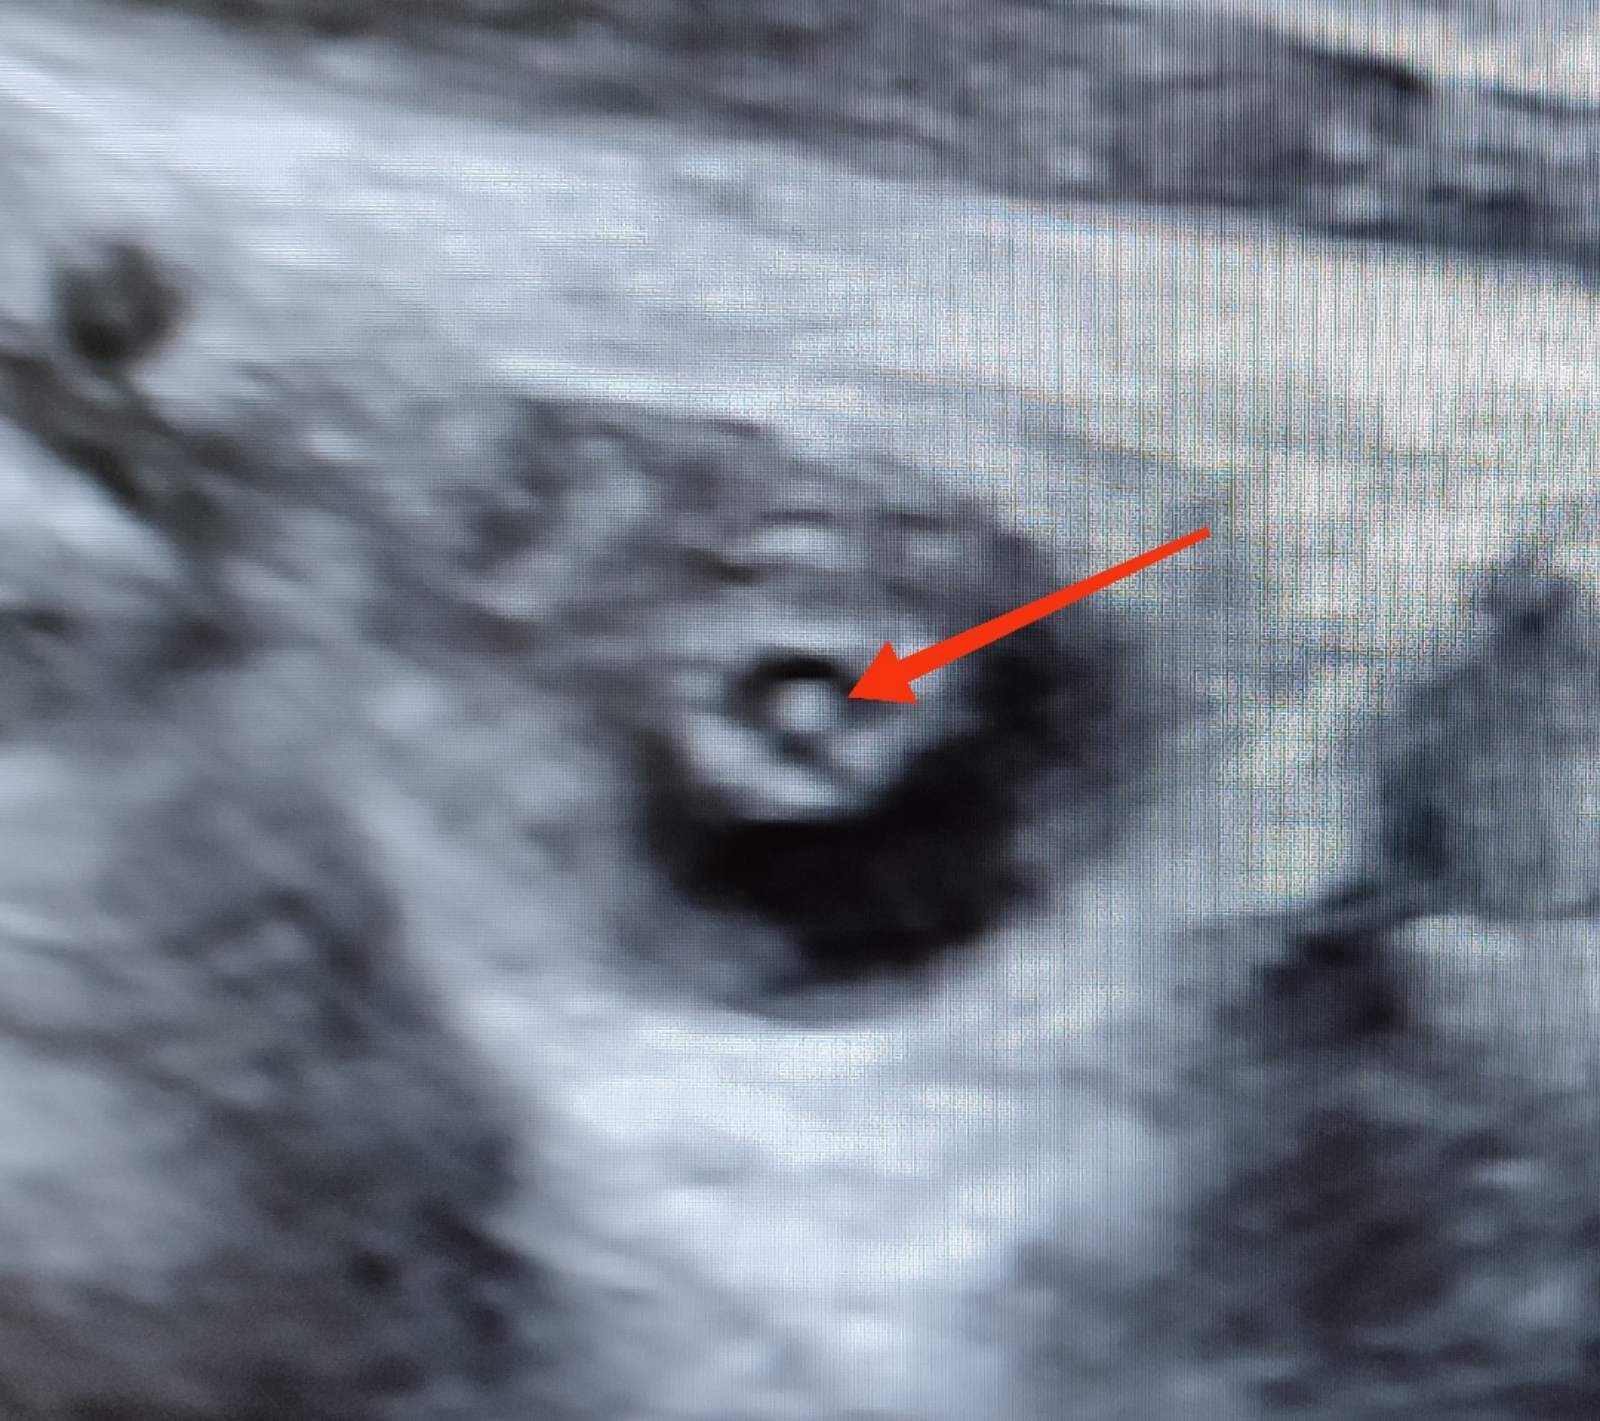

În cazul nostru, ecografia efectuată pe parcursul lunii iunie curent de către medicul imagist Svetlana Basova, la termenul 38 de săptămâni de sarcină a evidențiat la Cristalinul ochiului drept - o creșterea punctiformă a ecogenității în regiunea centrală a cristalinului (cataractă nucleară) iar la Cristalinul ochiului stâng – s-a determinat îngroșarea și creșterea ecogenității inelului periferic, completă (cataractă corticală).